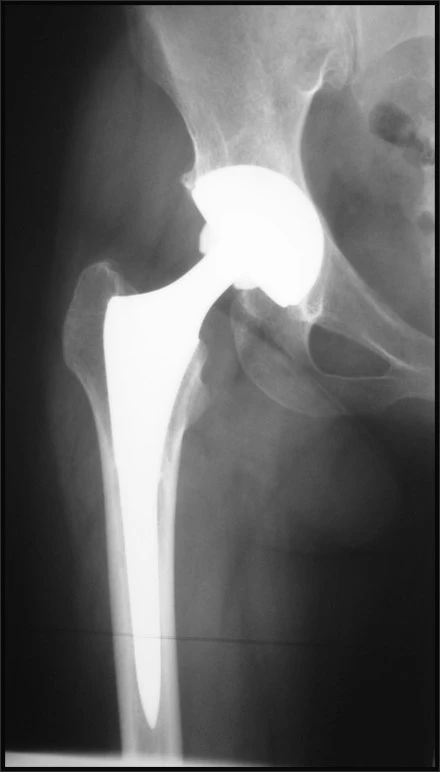

全髋关节:

1、生物固定型髋关节

2、水泥固定型髋关节

3、混合固定型髋关节

固定模式的发展:从人工髋关节发展的历史看,股骨假体固定模式从最初的压配型到Charnley的骨水泥型,再到生物固定型。